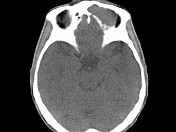

- 单项选择题男,53岁, 左眼痛、突出3年,结合图像, 最可能的诊断是 ( )

A、淋巴瘤

B、骨膜下脓肿

C、黏液囊肿

D、眼型Graves病

E、良性混合瘤